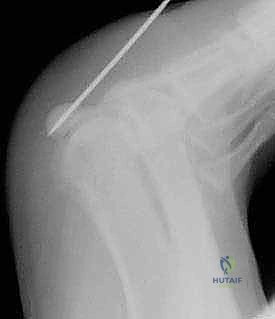

2. التصوير الإشعاعي (X-Rays)

الأشعة السينية هي الخطوة الأولى في التصوير. يتطلب الأمر زوايا تصوير خاصة (Axial Sesamoid View) لرؤية العظام السمسمية بوضوح دون تداخل مع عظام المشطية.

* تحدي تشخيصي: حوالي 10% إلى 30% من الناس لديهم عظمة سمسمية مقسمة خلقياً (Bipartite Sesamoid)، والتي تبدو في الأشعة وكأنها مكسورة. يميز الدكتور هطيف بين الكسر الحقيقي والتقسيم الخلقي من خلال فحص حواف العظمة (حواف الكسر تكون حادة وغير منتظمة، بينما حواف التقسيم الخلقي تكون ناعمة ومستديرة) ومقارنتها بالقدم السليمة.